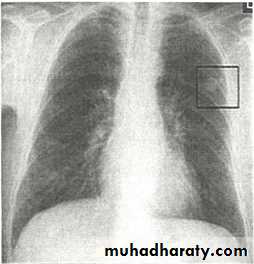

Chest X-ray shows radio-opaque (white) nodular lesion in the right mid-lung field.

Dx:x chicken pox , Histoplasmosis (calcified granuloma).